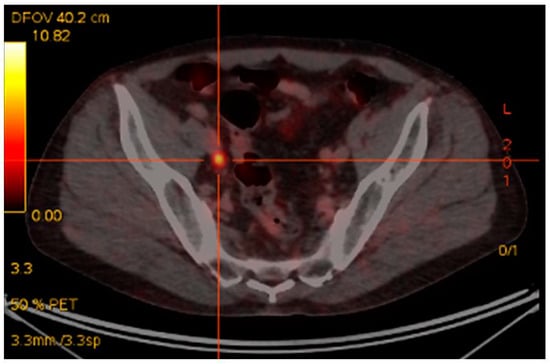

68Ga-PSMA PET/CT has recently been investigated as a potential staging modality in primary prostate cancer. Given that cellular PSMA expression has been shown to correlate with PSA and Gleason score [73] and 68Ga-PSMA PET/CT has been shown to be superior to standard staging modalities, such as CT, the use of 68Ga-PSMA PET/CT would seem to be a logical clinical extension in staging of primary disease. Early data appear to confirm this contention, with several studies [74,75], including our own [76], showing high rates of detection of CT occult early metastatic disease (Figure 2). In our recent study there was very good correlation between PSA and Gleason score and the chance of PSMA-avid metastatic disease. This finding correlates with other studies indicating a role in intermediate-to-high risk primary prostate cancer, with often occult nodal, and occasionally osseous, metastases identified. In assessment of potential bone metastases, 68Ga-PSMA PET/CT has been shown to be superior to bone scintigraphy in several studies [77,78].

Figure 2.

Staging 68Ga-PSMA PET/CT. Gleason 4 + 5. PSA 19 ng/mL. Intense 68Ga-PSMA avid primary disease in prostate with 68Ga-PSMA avid superficial left inguinal node metastasis.